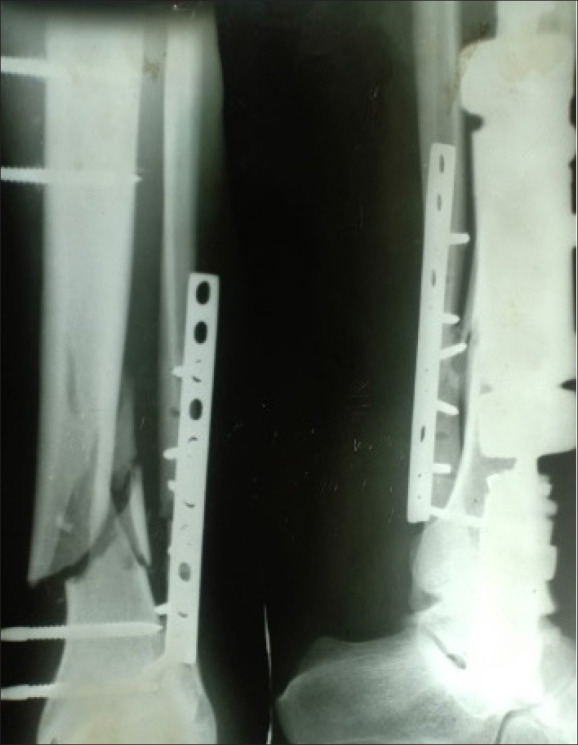

{"title":"Radiographic and functional results of Ilizarov fixation in the management of nonunion of tibia and femur fractures: a retrospective case series.","authors":"Mohamed A A Ibrahim, Khalid M Alhomayani, Usama Gaber, Hashem A Bukhary, Samir A Nematallah, Mostafa M Elgahel","doi":"10.5144/0256-4947.2024.146","DOIUrl":null,"url":null,"abstract":"<p><strong>Background: </strong>Femoral and tibial fractures may result in delayed union and nonunion, posing significant challenges in orthopedic practice. The Ilizarov technique has emerged as a promising solution for managing these complex cases.</p><p><strong>Objectives: </strong>Evaluate the radiographic and functional results of Ilizarov fixation in the treatment of nonunion of tibia and femur fractures.</p><p><strong>Design: </strong>Retrospective.</p><p><strong>Settings: </strong>Hospitals affiliated with a university hospital.</p><p><strong>Patients and methods: </strong>Patient demographics, fracture characteristics, and treatment details were analyzed for the period from October 2015 to September 2022 in patients who were treated for nonunion of the tibia and femur using the Ilizarov fixator. Clinical and radiological assessments were performed using the Association for the Study and Application of Methods of Ilizarov (ASAMI) criteria. The study focused on assessing the average duration for union and frame removal, bone results, successful union rates, and functional results using the ASAMI criteria, obtaining data from the existing medical records, spanning various medical facilities treating nonunion fractures.</p><p><strong>Sample size: </strong>126 patients.</p><p><strong>Results: </strong>The average duration for union and frame removal was 8 months, with excellent bone results observed in 60.32% of cases. Out of 126 patients, 118 achieved successful union, while there were 2 failure cases necessitating amputation (1.52%). Functional results revealed excellent outcomes in 39.68% of cases. Complications included pin tract infections, ankle and knee stiffness, and limb shortening. External fixation duration and infection eradication were consistent with previous research, emphasizing the technique's effectiveness.</p><p><strong>Conclusions: </strong>The Ilizarov technique proved highly effective in managing nonunion tibia and femur fractures, offering favorable outcomes in terms of union, infection control, pain relief, and functional recovery. While excellent bone outcomes do not guarantee optimal function, this method remains a reliable approach for complex cases.</p><p><strong>Limitations: </strong>Potential biases inherent in retrospective analyses and the need for further randomized controlled trials to comprehensively compare treatment modalities.</p>","PeriodicalId":93875,"journal":{"name":"Annals of Saudi medicine","volume":"44 3","pages":"146-152"},"PeriodicalIF":0.0000,"publicationDate":"2024-05-01","publicationTypes":"Journal Article","fieldsOfStudy":null,"isOpenAccess":false,"openAccessPdf":"https://www.ncbi.nlm.nih.gov/pmc/articles/PMC11268481/pdf/","citationCount":"0","resultStr":null,"platform":"Semanticscholar","paperid":null,"PeriodicalName":"Annals of Saudi medicine","FirstCategoryId":"1085","ListUrlMain":"https://doi.org/10.5144/0256-4947.2024.146","RegionNum":0,"RegionCategory":null,"ArticlePicture":[],"TitleCN":null,"AbstractTextCN":null,"PMCID":null,"EPubDate":"2024/6/6 0:00:00","PubModel":"Epub","JCR":"","JCRName":"","Score":null,"Total":0}

Patients and methods: Patient demographics, fracture characteristics, and treatment details were analyzed for the period from October 2015 to September 2022 in patients who were treated for nonunion of the tibia and femur using the Ilizarov fixator. Clinical and radiological assessments were performed using the Association for the Study and Application of Methods of Ilizarov (ASAMI) criteria. The study focused on assessing the average duration for union and frame removal, bone results, successful union rates, and functional results using the ASAMI criteria, obtaining data from the existing medical records, spanning various medical facilities treating nonunion fractures.

Results: The average duration for union and frame removal was 8 months, with excellent bone results observed in 60.32% of cases. Out of 126 patients, 118 achieved successful union, while there were 2 failure cases necessitating amputation (1.52%). Functional results revealed excellent outcomes in 39.68% of cases. Complications included pin tract infections, ankle and knee stiffness, and limb shortening. External fixation duration and infection eradication were consistent with previous research, emphasizing the technique's effectiveness.

Conclusions: The Ilizarov technique proved highly effective in managing nonunion tibia and femur fractures, offering favorable outcomes in terms of union, infection control, pain relief, and functional recovery. While excellent bone outcomes do not guarantee optimal function, this method remains a reliable approach for complex cases.